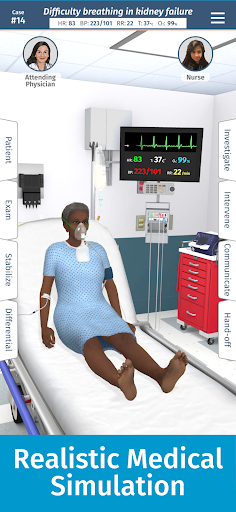

• Hơn 20 hình đại diện thực tế, bao gồm bệnh nhi và người lớn

Đào tạo mô phỏng theo yêu cầu của Full Code với các bệnh nhân ảo thực tế cho phép bạn thực hành các trường hợp phức tạp và nâng cao kỹ năng của mình bất cứ khi nào bạn có thời gian nghỉ ngơi, bất kể bạn ở đâu, trên các thiết bị bạn đã sở hữu. CẢI THIỆN SỰ TỰ TIN

Bệnh nhân và cảnh của chúng tôi trông và âm thanh chân thực hơn bao giờ hết.